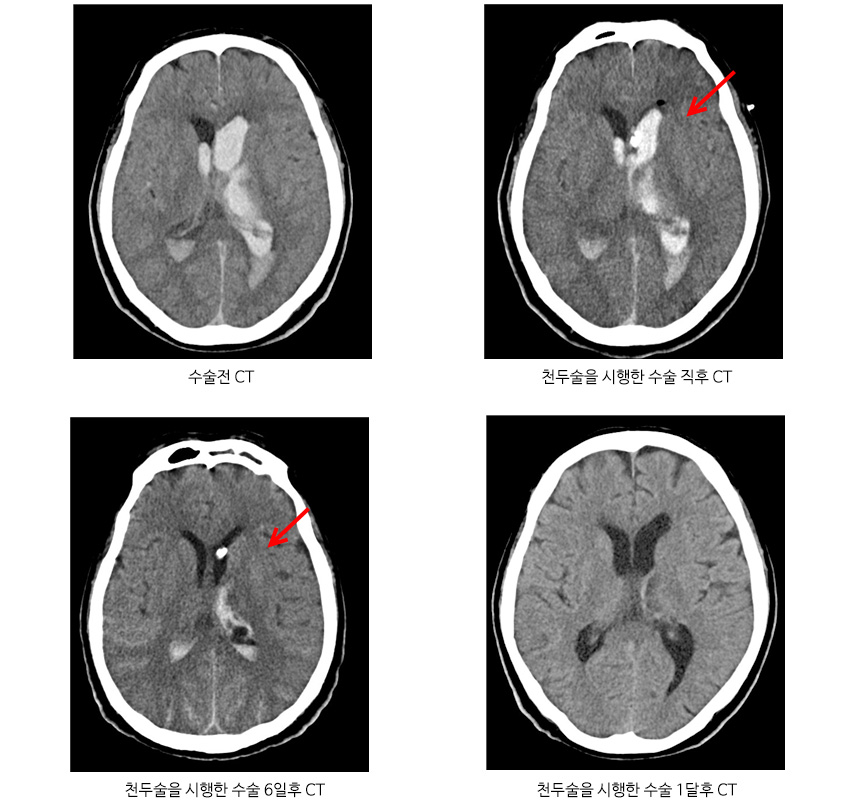

치료는 고혈압성 뇌출혈인 경우에는 혈종의 크기와 환자의 상태에 따라 치료법이 달라지며 혈종 크기가 작은 경우 약물치료를 시행하고, 혈종 크고 마비가 있는 경우 두개골에 구멍을 내서 관을 삽입하여 혈종을 배액시키는 수술법이 있습니다.

만성 경막하출혈 CT